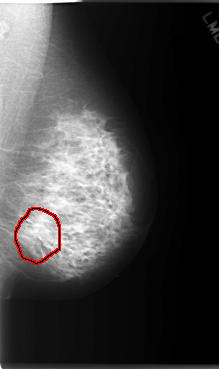

C_0070_1.LEFT_MLO

LEFT_MLO LINES 5904 PIXELS_PER_LINE 3504 BITS_PER_PIXEL 12 RESOLUTION 50 OVERLAY

FILE: C_0070_1.LEFT_MLO.OVERLAY

TOTAL_ABNORMALITIES 1

ABNORMALITY 1

LESION_TYPE MASS SHAPE ARCHITECTURAL_DISTORTION MARGINS N/A

ASSESSMENT 4

SUBTLETY 1

PATHOLOGY MALIGNANT

TOTAL_OUTLINES 1

BOUNDARY